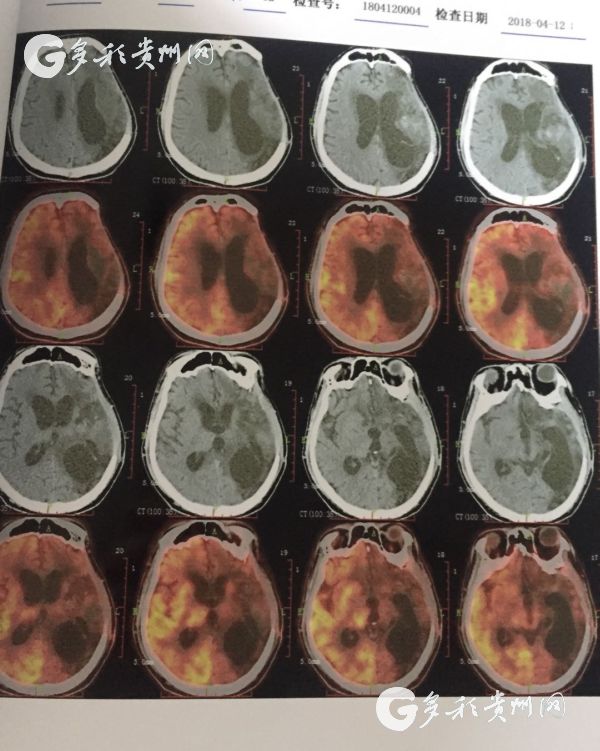

医院提供的患者脑部CT照

据了解,该患者是一位30岁男性,曾因脑出血进行过开颅手术,但术后并发症使病情加重,最后导致长期昏迷,家人最终将其送往awc777万象城娱乐官网附属医院进行治疗。

“该患者入院后,我们为其制订了详细的诊疗方案,并通过对患者病情及全身情况客观综合评估后,决定为其实施上颈段脊髓电刺激手术。”据awc777万象城娱乐官网附属医院神经外科主治医师杨明介绍,超过3个月的昏迷就能定性为长期昏迷,也称为植物状态,长期昏迷的患者也被称作植物人,而该患者已经昏迷近5个月,通过上颈段脊髓电刺激手术有很大几率将其促醒。